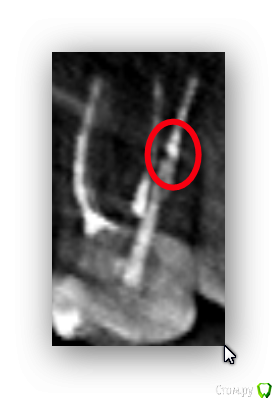

freeman22 Опубликовано 27 октября, 2015 Автор Поделиться Опубликовано 27 октября, 2015 Посмотрите пожалуйста ещё под этой проекцией, там всё нормально (где я выделил)? http://s017.radikal.ru/i401/1510/41/87acd0687e83.pnghttp://s013.radikal.ru/i324/1510/3e/028a8af12ff7.png Ссылка на комментарий

freeman22 Опубликовано 27 октября, 2015 Автор Поделиться Опубликовано 27 октября, 2015 Что Вас беспокоит? Меня беспокоит начавшаяся после установки штифта и пломбы ноющая, отдающая в другие зубы боль (уже второй месяц!)! В общем дошёл уже до КТ)) но в плане пролечённого зуба врачи ничего плохого не нашли, в том числе и на КТ. В общем врачи у которых я был сходятся во мнение, что всему виной щели между зубами и глубокие десневые карманы, в которые попадает пища и она взывает такую боль.Один врач предложила снять пломбу и штифт и поставить на зуб керамическую накладку.Другой вариант и он мне кажется более правильным - обточить зуб со штифтом и надеть на него металлокермиечкую коронку. Ну то есть сделать зазоры между зубами минимальным.Что вы можете посоветовать в данной ситуации? Снимок со щелями.http://s018.radikal.ru/i520/1510/ae/0578f8935f80.png Ссылка на комментарий

DmitrySH Опубликовано 27 октября, 2015 Поделиться Опубликовано 27 октября, 2015 С учетом разрушения зуба, второй вариант более правильный. По данному снимку совсем не ясно состояние контактов между зубами. Тут сложно что-то сказать.Но раз болит, то сделайте на зуб нормальную временную коронку чтоб ничего не забивалось. Если через некоторое время боли пройдут - то постоянную. Если будут продолжаться, то убирать пломбу со штифтом и смотреть. 1 Ссылка на комментарий